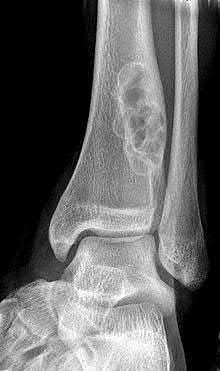

ORTHOPEDIC MCQS ONLINE 015FOOT and Ankle CLINICAL SITUATION FOR QUESTIONS 1 THROUGH 4 A B Figures 1a and 1b a…